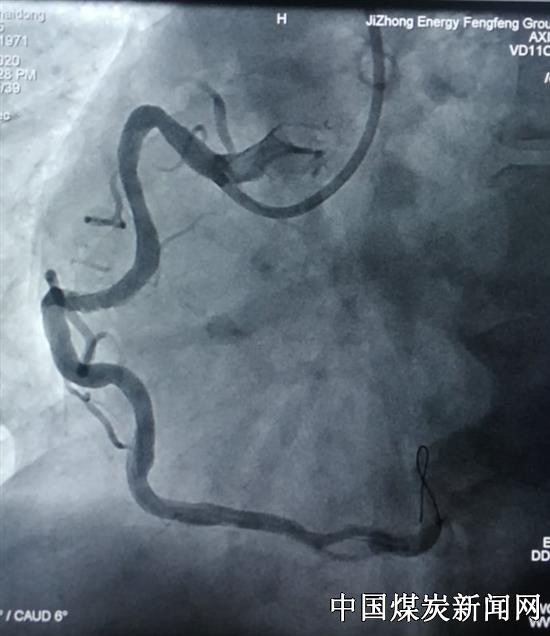

王溥和李玲商议决定先给患者经指引导管给药进行冠脉内溶栓降低了出血风险。血管出现部分再通后,导丝终于通过了闭塞病变,到达了血管远段,成功地为病人在迂曲且狭窄最重部位植入了支架。这名患者右冠状动脉非常粗,梗死面积极大,如果不及时开通闭塞血管,患者死亡危险高,还会导致残疾。